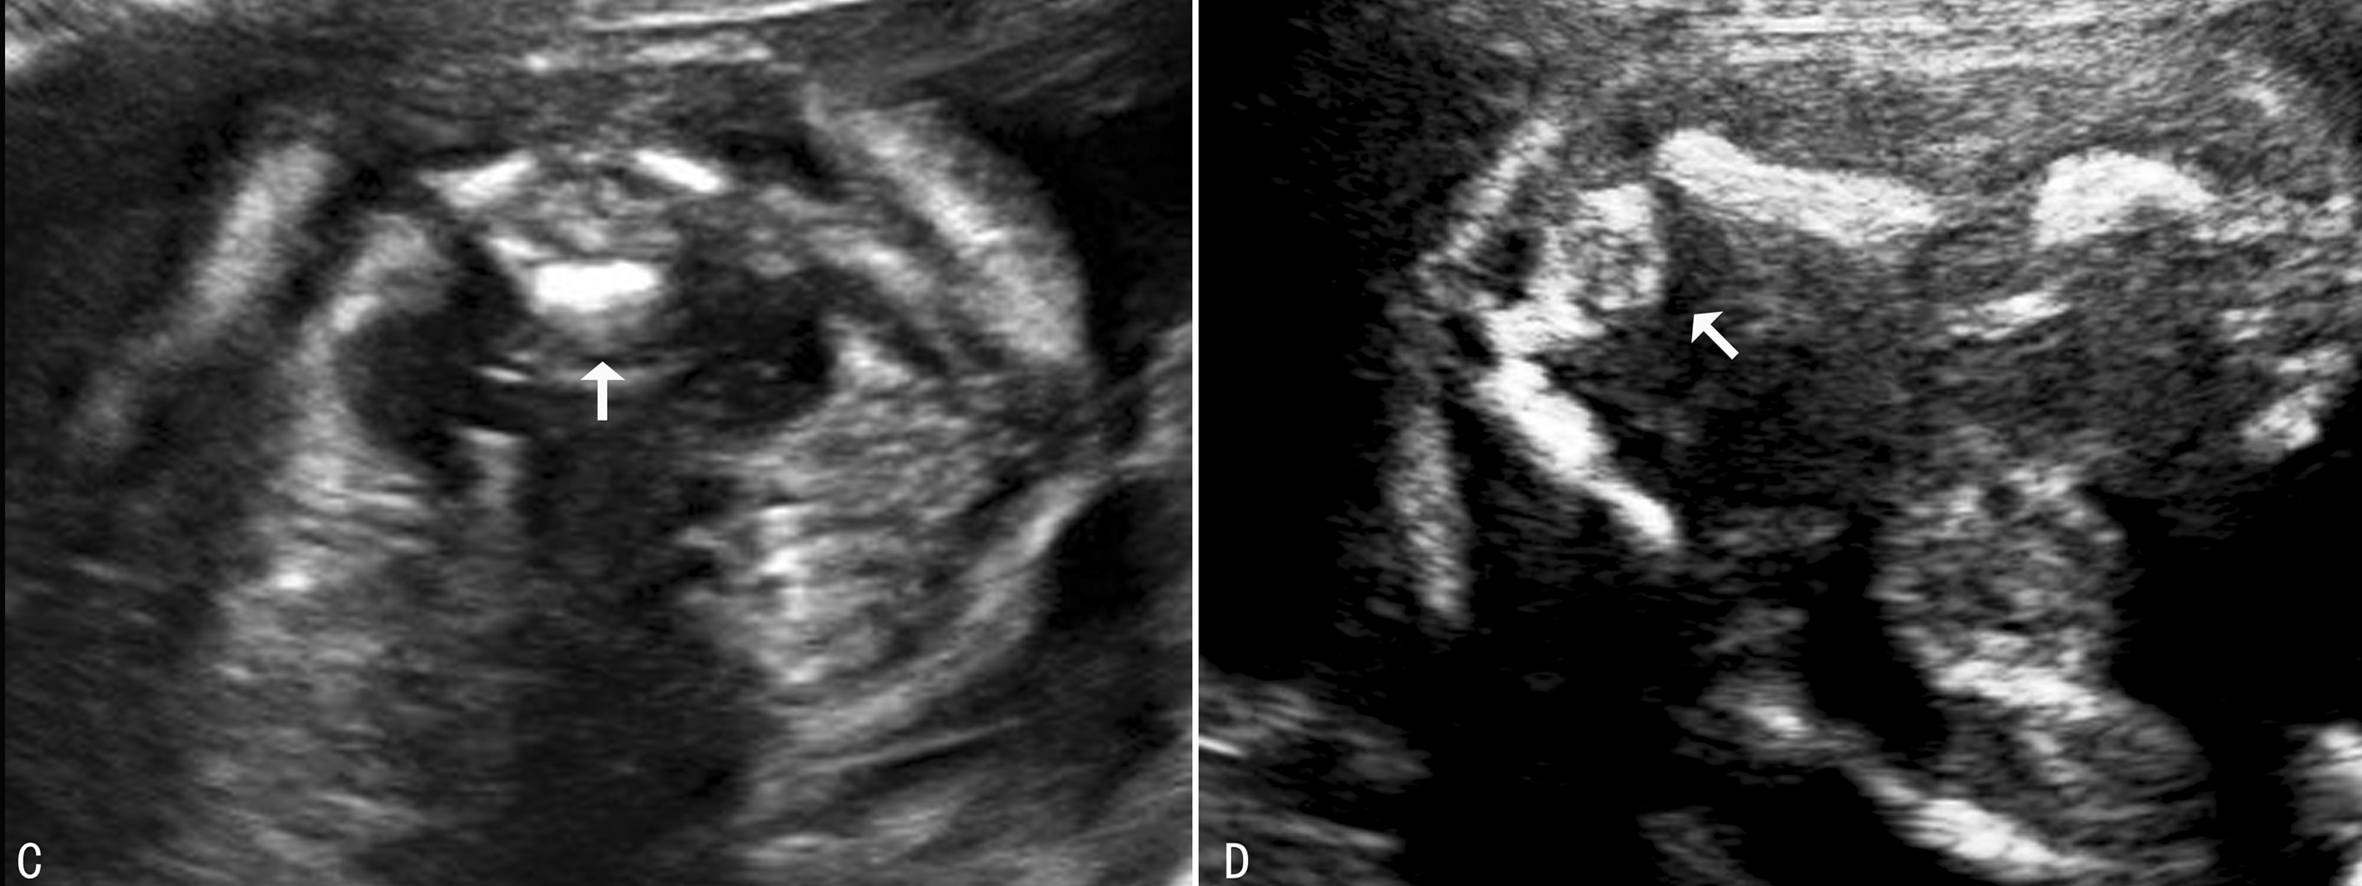

超声显像检查时需要观察矢状切面、横切面和冠状切面(图3,4)。矢状切面显示椎体及一侧椎弓的骨化中心呈现两条串珠状的平行线,在骶尾部收拢合并,因为一个切面只能显示一侧的椎弓,需动态扫描使两侧椎弓都能显示;[f2] 横切面的扫查需要耐心仔细从颈椎到骶尾部依次进行,不同的椎体超声表现不同,第一颈椎呈四边形或圆钝的三角形(图3A),其他呈现等腰三角形,尖端为椎体,指向胎儿腹侧(图3B,图4C、D)。冠状切面,声束靠近皮肤显示两排平行的骨化中心,是双侧椎弓,声束再向胎儿腹侧扫查,可显示一排椎体(图5),透明三维显示可以直观地显示胎儿脊柱的空间结构和形态(图6)。扫查时要注意覆盖在脊柱上的皮肤的完整性,以免遗漏微小的脊柱裂或者隐形脊柱裂,隐形脊柱裂有时仅表现为皮肤鼓起的小泡状无回声。

图4 腰椎横断面(C)及骶椎横断面(D)

图5 脊柱冠状切面声像图(箭头示髂骨翼,1为椎弓,2为椎体)

图6 脊柱三维显示